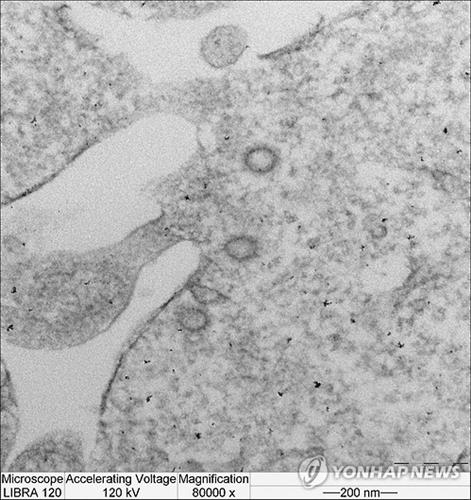

(서울=연합뉴스) 이 율 기자 = 중동호흡기증후군(메르스) 후보 백신이 독일에서 연말부터 처음으로 임상시험에 들어간다.

메르스 바이러스에 대한 백신은 아직 개발되지 않았으며 세계보건기구는 후보 백신들이 사전임상단계까지 개발된 상태라고 밝힌 바 있다.